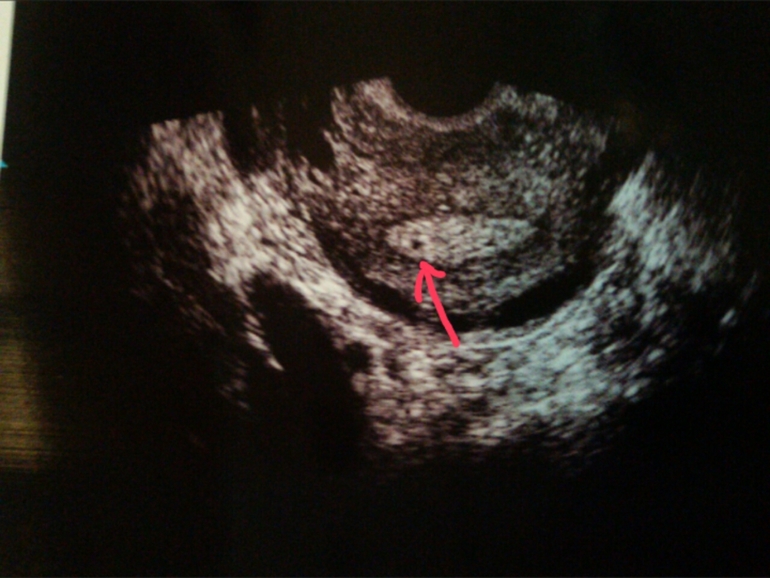

Итак. Единственное, что меня порадовало, это эндометрий - 9,7 мм. Давно я у себя такого эндика не наблюдала, обычно не больше 5-6. Ну и то, что острого течения эндометрита больше не наблюдается (ну надо полагать, столько вколола/выпила).

Не понятно, была ли О вообще.

Доминантных фолликов нет, только 3-4 мм.

Жидкости в позадиматочном пространстве нет.

Желтого тела нет, видимо из-за прогестероновой недостаточности

А потом вообще затихла и долго-долго что-то рассматривала. И сказала: "Какую-то точку размером 2 мм вижу. Не полип, не миома. Но и беременность, по идее, не могу так рано увидеть".